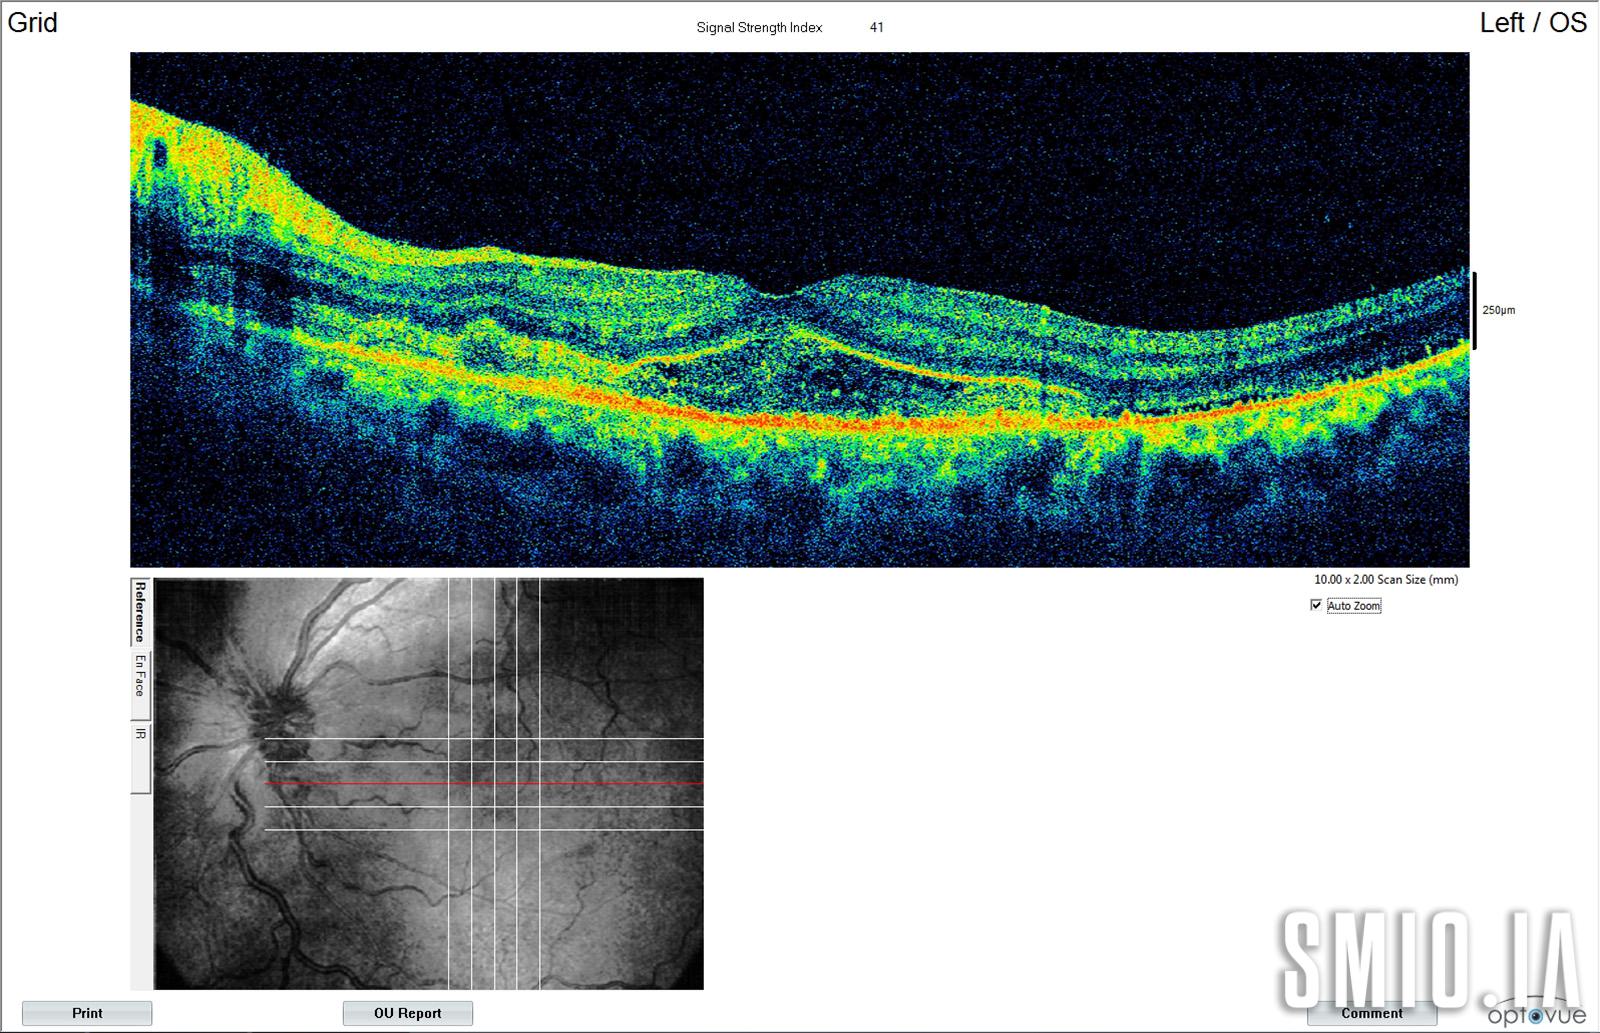

Description: La Choroï-rétinopathie hypertensive présente cliniquement avec des décollement rétinien séreux et des lésions de l'épithélium pigmentaire rétinien jaunâtre 4 jours après l'accouchement chez une femme 28 qui présente le jour de l'accouchement baisse de l'acuité visuelle bilatérale. Sa pression artérielle était de 174/97 mm Hg et l'OCT a montré un liquide sous-rétinien et rétinien avec une exsudation fibrinoïde.

Appareil d'imagerie: Zeiss Visucam 500 OCT Optovue